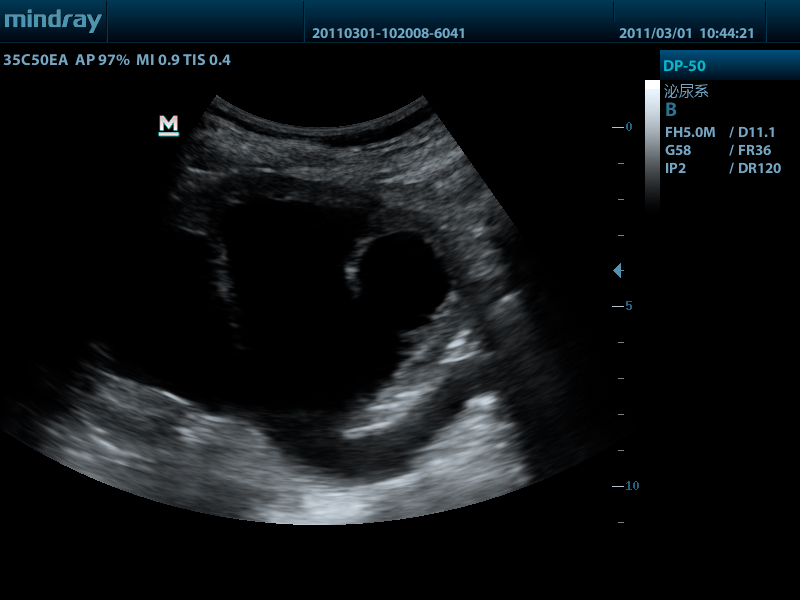

- Конвексный датчик 35C50EA, 1.7 - 6.0 МГц, радиус кривизны 50 мм